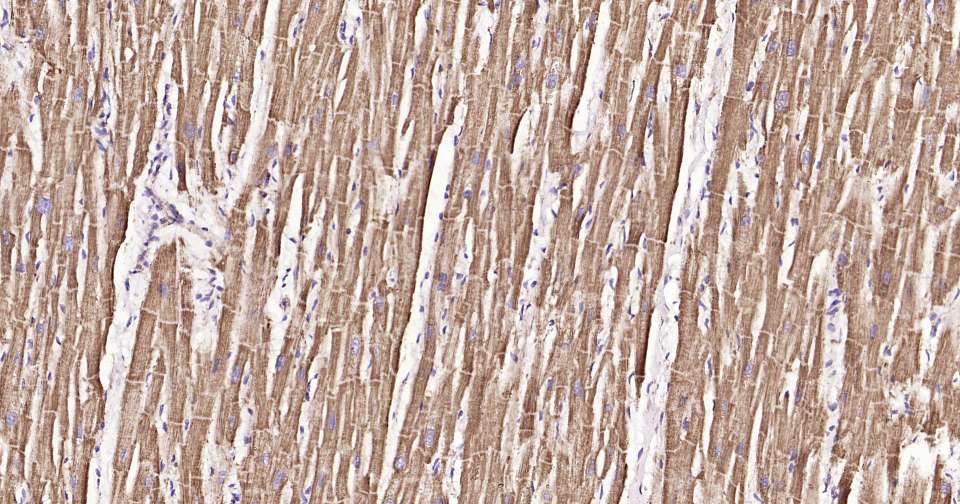

Immunohistochemical analysis of paraffin embedded mouse heart tissue slide using IHC0317 (HSP60 Kit).

Immunohistochemical analysis of paraffin embedded human heart tissue slide using IHC0317 (HSP60 Kit).

Immunohistochemical analysis of paraffin embedded rat heart tissue slide using IHC0317 (HSP60 Kit).